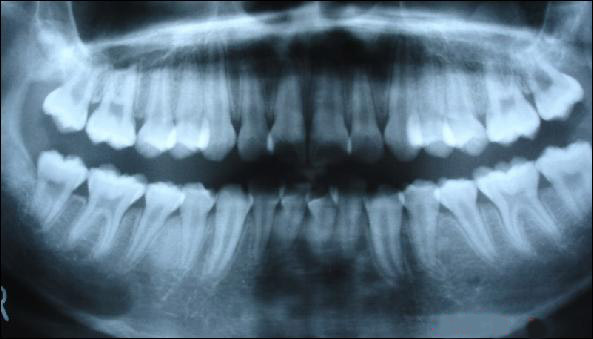

上圖為健康人的全口曲面斷層片,俗稱骷髏片